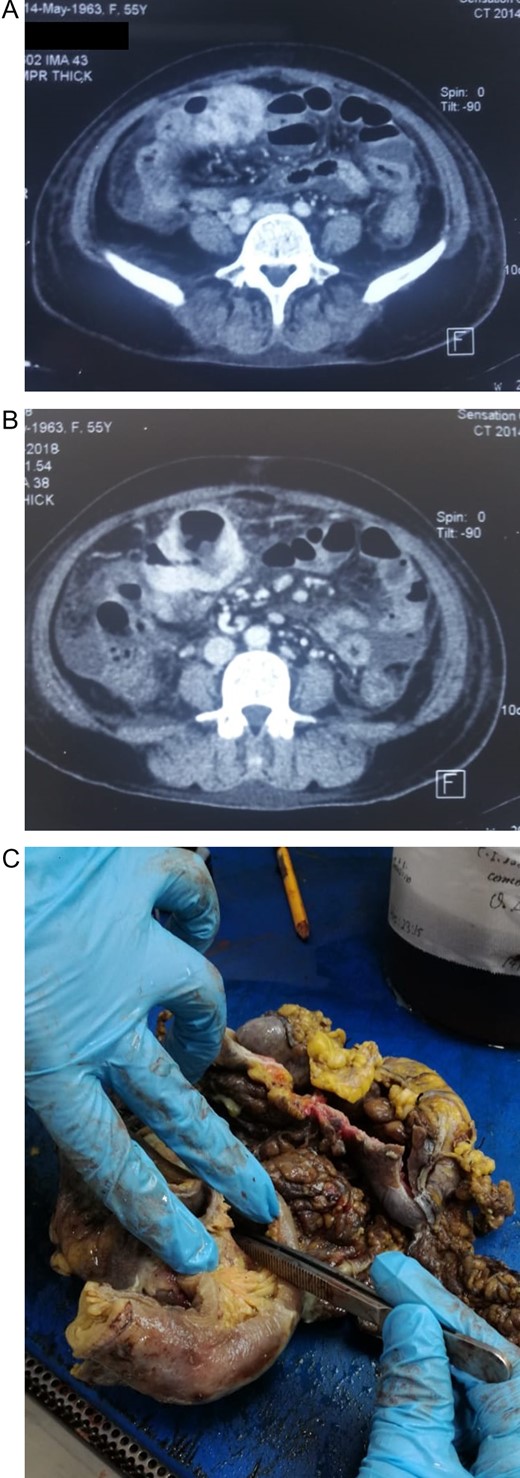

Patient is a 55-year-old female who presented to the emergency department with abdominal pain. She had been experiencing diffuse mild abdominal pain for the past year and reported that in the last 4 months the pain became more intense and was experiencing weight loss. On clinical examination, a dehydrated, malnourished and tachycardic patient with abdominal tenderness and a mass in the abdomen was discovered. She had leukocytosis with neutrophilia, and a heterogeneous mass with peripheral vascularity attached to the small bowel was revealed by echography. A contrast-enhanced CT confirmed a 10 × 11 × 5 cm3 mass in the transverse colon near the hepatic flexure that invaded the small bowel mesentery (Fig. 1A). The mass had a cavity filled with fluid and gas. Free abdominal fluid and some dilated loops of bowel were also observed (Fig. 1B). With these findings and after adequate resuscitation, surgery was decided. At laparotomy, 300 ml of purulent liquid in the abdominal cavity and a 10 × 10 × 5 cm3 blueish colonic mass, near the hepatic flexure that invaded the jejunum 50 cm distal to the ligament of Treitz, was discovered. Also, a 1 × 2 cm2 perforation was found in the mass from where fecaloid fluid poured into the abdomen. During surgery, an en-bloc resection of the colonic mass with the compromised jejunum was completed, the intestinal transit was restored with mechanical staples and an exhaustive washing of the abdominal cavity was done. Also, a drain was left near the colonic anastomosis. Pathology reported a 10 × 10 × 5 cm3 inflammatory colonic mass (Fig. 1C). The wall of the colon had necrotic patches (Fig. 2A). The jejunum wall had an inflammatory reaction that narrowed its lumen, nevertheless, no necrosis was found (Fig. 2B). The 3 × 3 × 2 cm3 cavity in the colonic mass contained purulent material and two adult Ascaris lumbricoides of 15 and 7 cm (Fig. 2C), one of which had multiple eggs in its uterine tubule (Fig. 3A). Beside this cavity, a 1 × 2 cm2 perforation was discovered. Bowel perforation due to roundworms, with colonic wall necrosis, was the final diagnosis.

(A) CT revealing a mass in the colon that invaded the small bowel mesentery. (B) Colonic mass, with a cavity filled with fluid and gas. (C) Colonic mass and jejunum, colon with multiple ischemic and necrotic patches.